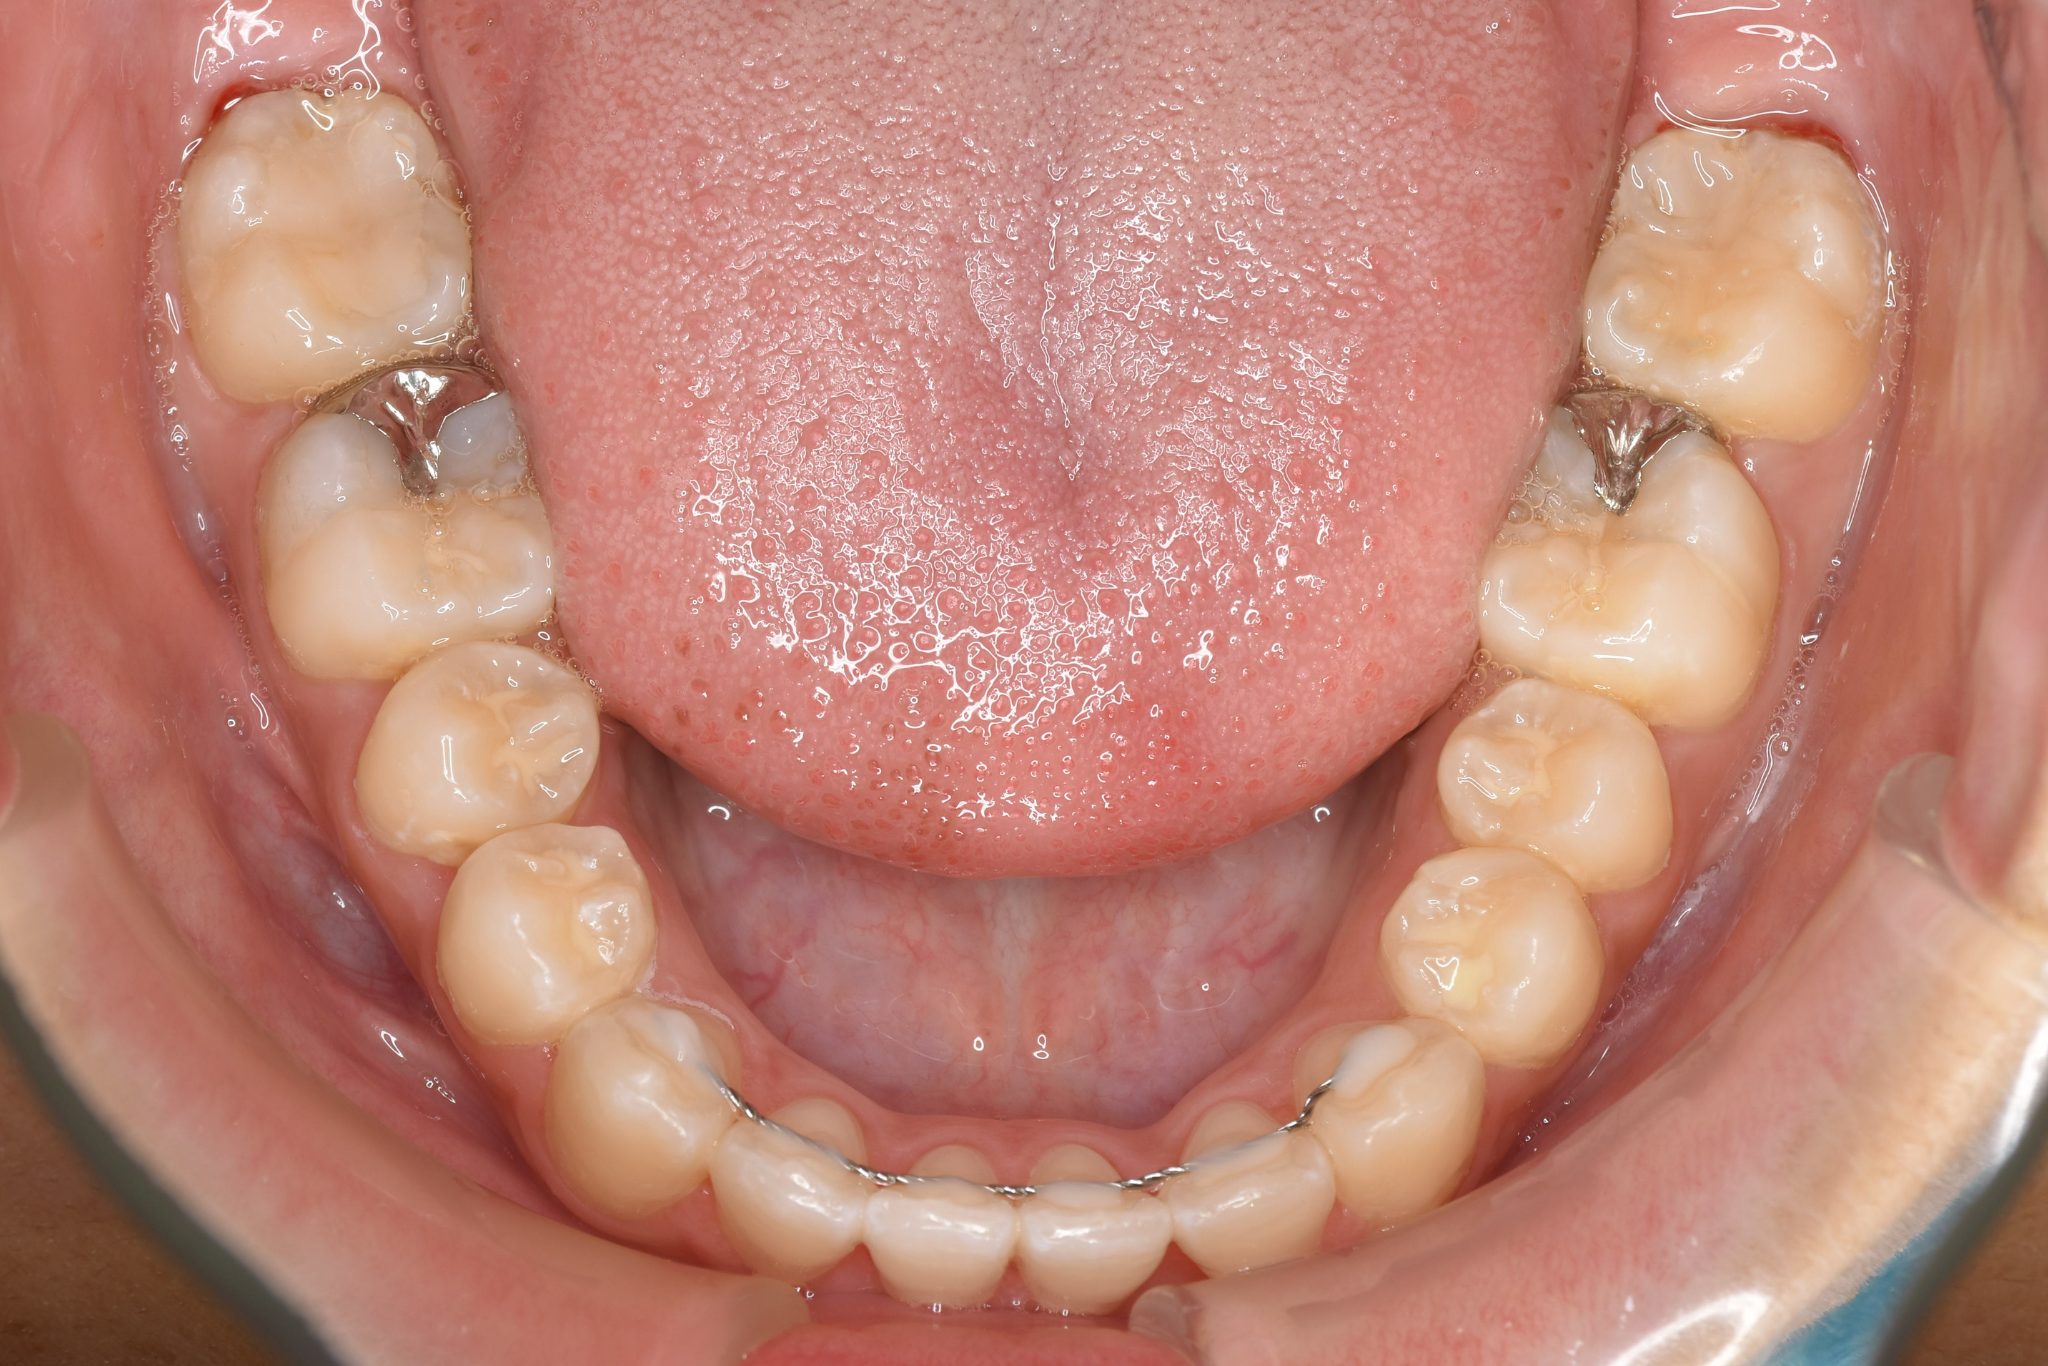

全顎ワイヤー矯正 症例_839